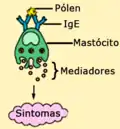

O desenvolvimento de alergias é uma combinação de herança genética e de exposição a fatores ambientais. A rinite alérgica é geralmente desencadeada por alergénios ambientais, como o pólen, pelo de animais, pó ou bolor.[3] O mecanismo subjacente envolve a ligação de anticorpos IgE ao alergénio, o que causa a libertação de químicos inflamatórios dos mastócitos, como a histamina.[2] O diagnóstico geralmente tem por base o historial clínico em conjugação com provas de sensibilidade cutânea ou análises ao sangue para detectar anticorpos IgE específicos. No entanto, estes testes apresentam frequentemente falsos positivos.[4]

A febre dos fenos, tal como todas as alergias, é uma resposta exagerada do sistema imunitário a um alergéneo, que geralmente é uma substância inócua e na maioria das pessoas não desencadeia uma resposta imune. Este tipo de resposta é designada por reacção de hipersensibilidade tipo 1.

Nas pessoas alérgicas, o pólen é inspirado e entra em contacto com a mucosa das vias aéreas. Aí, liga-se a anticorpos do tipo IgE que estão na parede de um tipo especial de glóbulos brancos, os mastócitos, fazendo com que sejam libertados vários compostos tais como a histamina, que actuam como mediadores inflamatórios.[17] São estes mediadores que causam os sintomas da febre dos fenos.